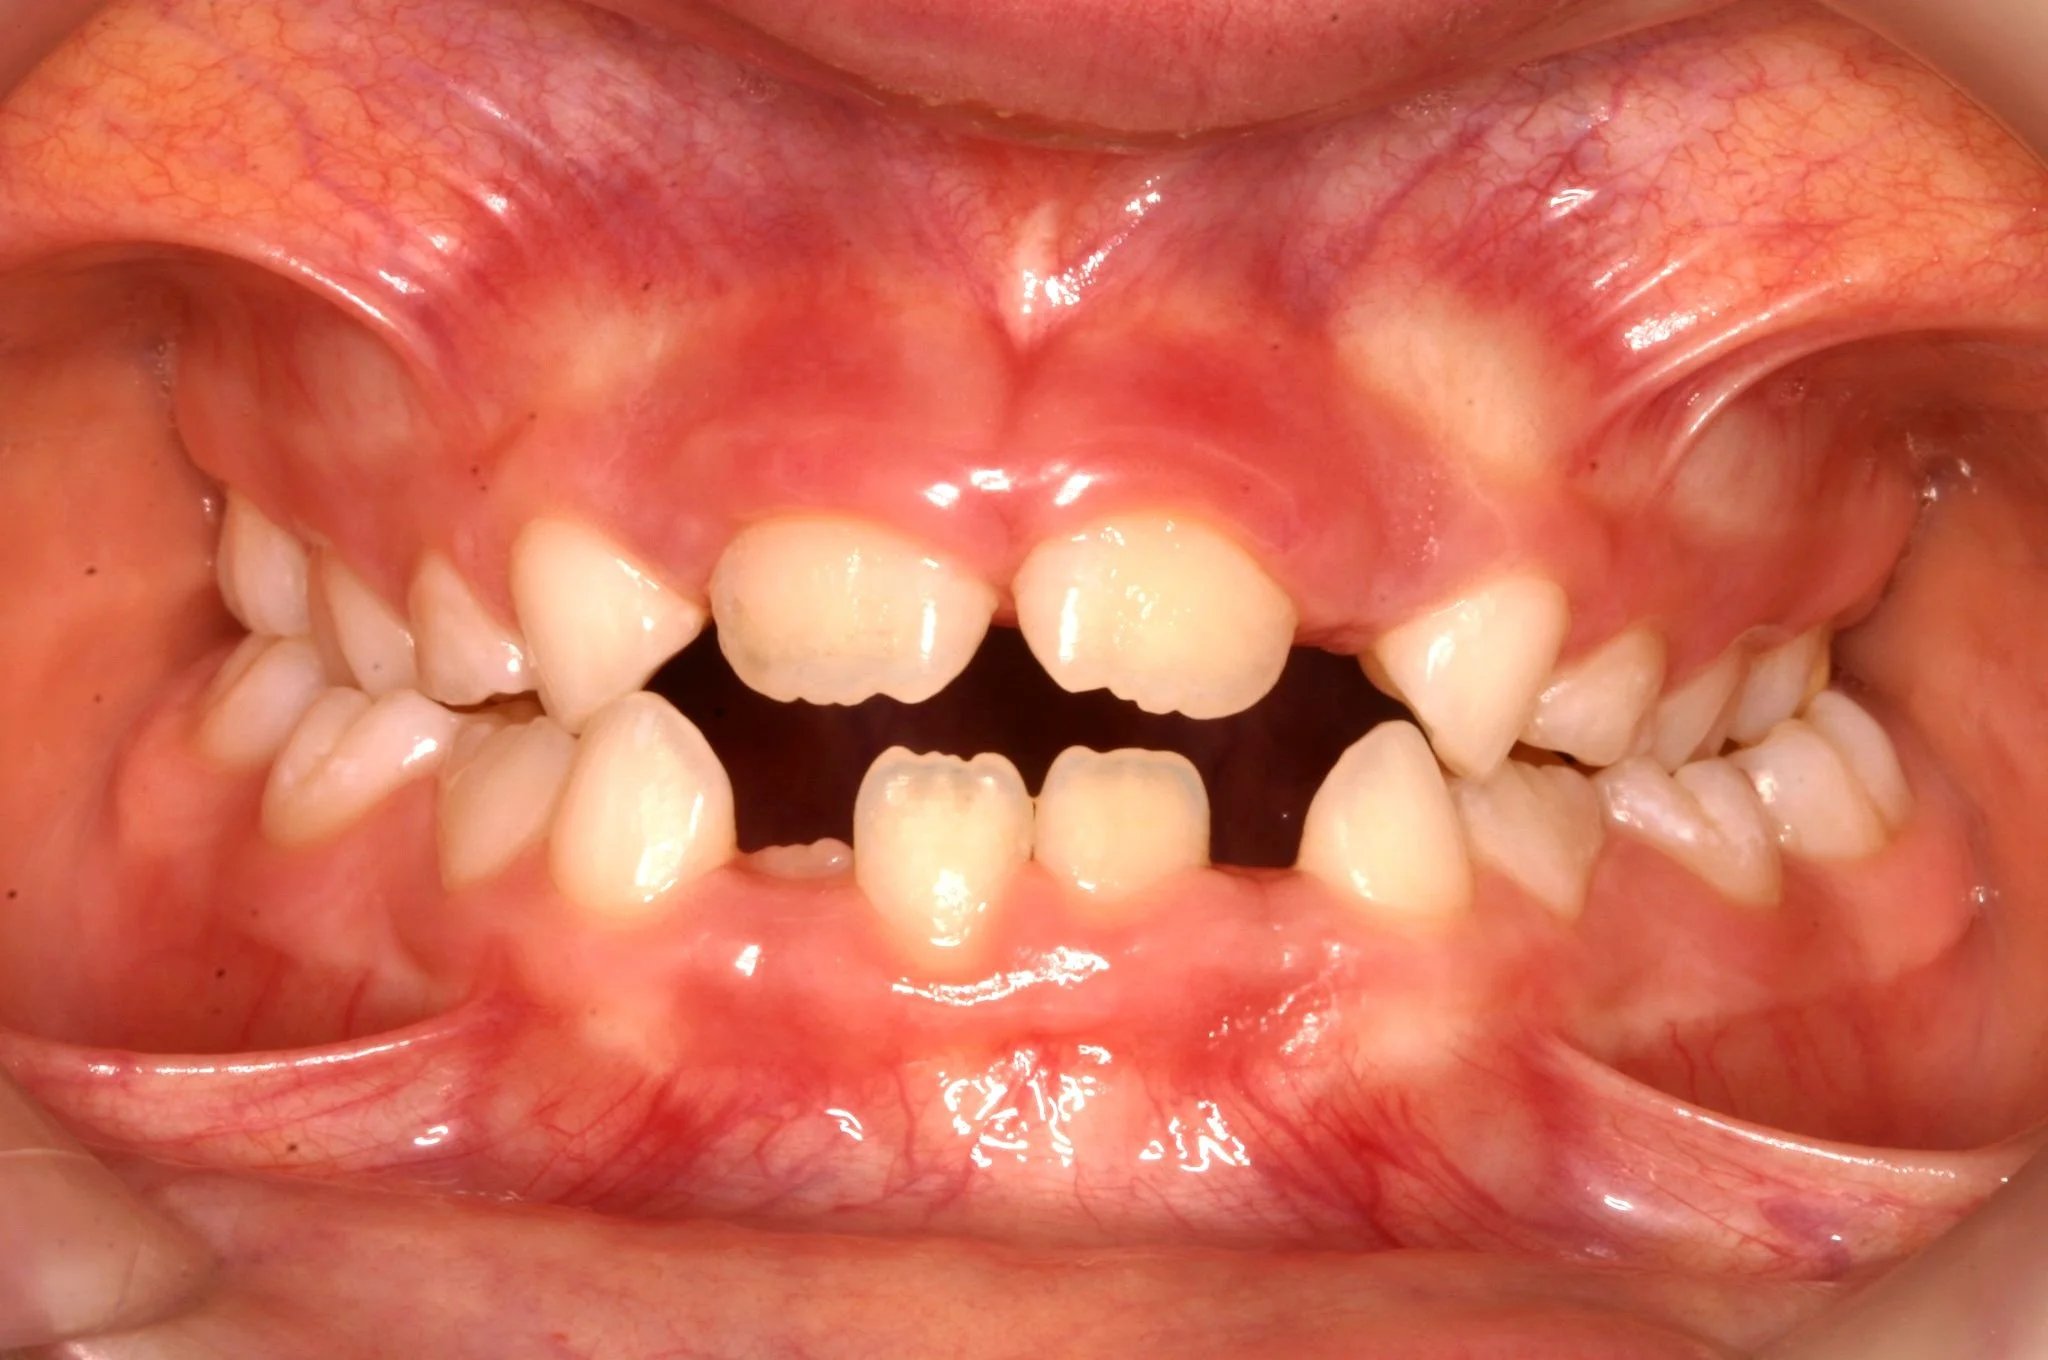

ORTODONZIA INTERCETTIVA + ALLINEAMENTO

BEFORE

Caso di una paziente con morso aperto iniziale e palato stretto, trattato in giovane età con terapia intercettiva mediante espansione rapida del palato. Successivamente, in adolescenza, è stata sottoposta a trattamento ortodontico fisso in dentatura permanente.